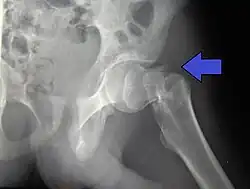

Subcapital fracture in a 92-year-old woman

X-rays of the affected hip usually make the diagnosis obvious; AP (anteroposterior) and lateral views should be obtained.

Intracapsular femoral head AO 31-C1 – 31-C3 Pipkin classification

femoral neck Subcapital AO 31-B1 – 31-B3 Garden classification, Pauwel's classification